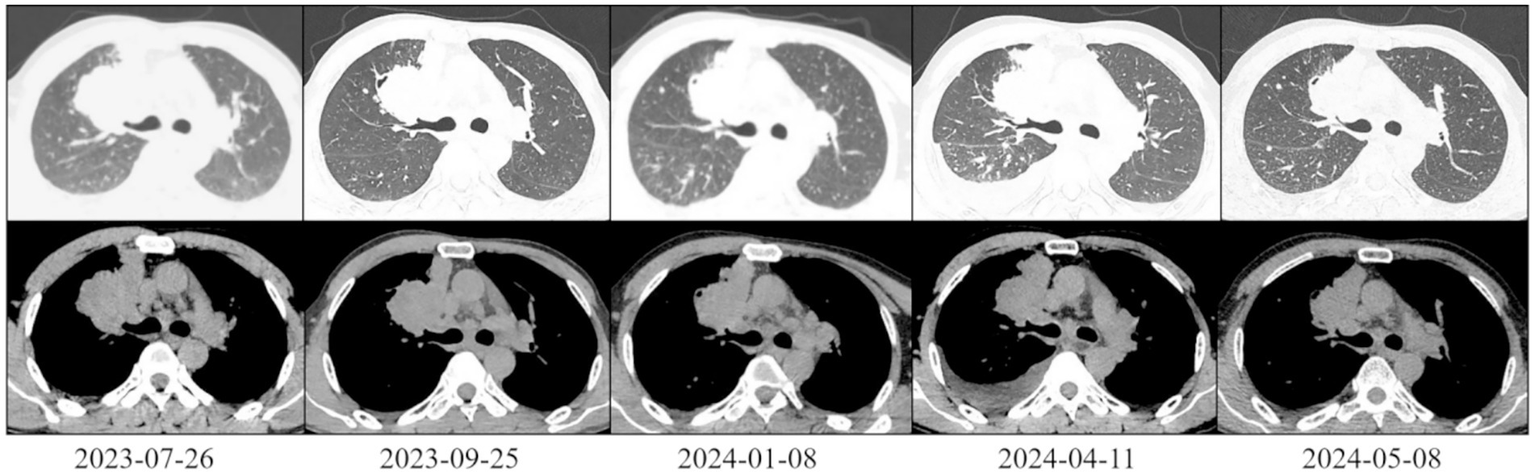

Figure 2

Chest CT scan of the patient (lung and mediastinal windows).

On 25 September 2023, after two cycles of treatment, the patient’s symptoms had improved significantly. His lower limb muscle strength had recovered, enabling him to walk independently instead of using a wheelchair. An imaging assessment revealed that the brain metastasis tumour measured 3.3 cm × 2.8 cm (Figure 1). The primary tumour measured 6.2 cm × 4.0 cm and showed new cavitary changes (Figure 2).

On 8 January 2024, after seven treatment cycles, the patient had improved muscle strength in the left upper limb and was able to walk independently, carry heavy objects and perform fine motor skills. The ECOG PS score was 0. Imaging assessment showed that the brain metastasis tumour measured 2.8 cm × 2.6 cm (Figure 1), while the primary tumour measured 5.4 cm × 3.9 cm (Figure 2).

On 11 April 2024, after 11 cycles of treatment: The patient’s symptoms remained unchanged with an ECOG PS score of 1. Serological testing/tumour markers: CEA: 11.20 ng/mL, NSE: 42.10 ng/mL, CYFRA21-1: 7.98 ng/mL. Imaging assessment: Brain metastasis measures 2.9 cm × 2.8 cm (Figure 1). The primary lung tumour measures 6.0 cm × 4.1 cm (Figure 2). There is a small amount of newly detected pleural effusion on the right side and moderate pericardial effusion. We concluded that the tumour had progressed and had become resistant to anlotinib. Following a consultation with the multidisciplinary team, we performed a pericardial puncture and drainage to relieve symptoms of fluid accumulation. The antitumour treatment regimen was then adjusted to include 800 mg of pemetrexed disodium and 600 mg of bevacizumab intravenously every 3 weeks.

On 6 May 2024, 20 days after chemotherapy, the tumour markers were as follows: CEA: 10.40 ng/mL, NSE: 35.10 ng/mL, CYFRA21-1: 2.98 ng/mL, SCC: 1.50 ng/mL. The imaging assessment revealed a primary lung tumour measuring 5.6 cm × 2.4 cm with no fluid accumulation (Figure 2), indicating treatment efficacy. Treatment with the original regimen (pemetrexed disodium + bevacizumab) continued on 9 May 2025.